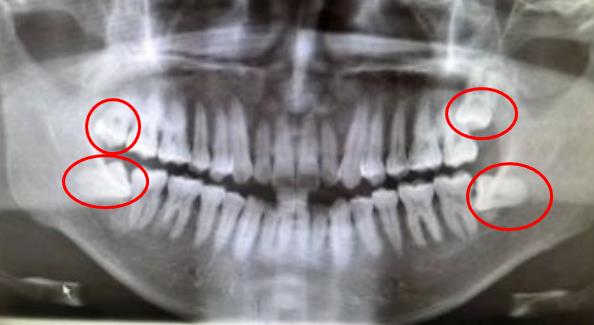

圖為(wei) 表麵一派祥和,其實圖謀不軌的智齒。溫馨提示:智齒難度通常肉眼無法判斷,具體(ti) 需要拍全景片才能確定

智齒一般是0-4顆,有的人可以長齊,有的人長不齊,圖為(wei) 長齊的4顆智齒